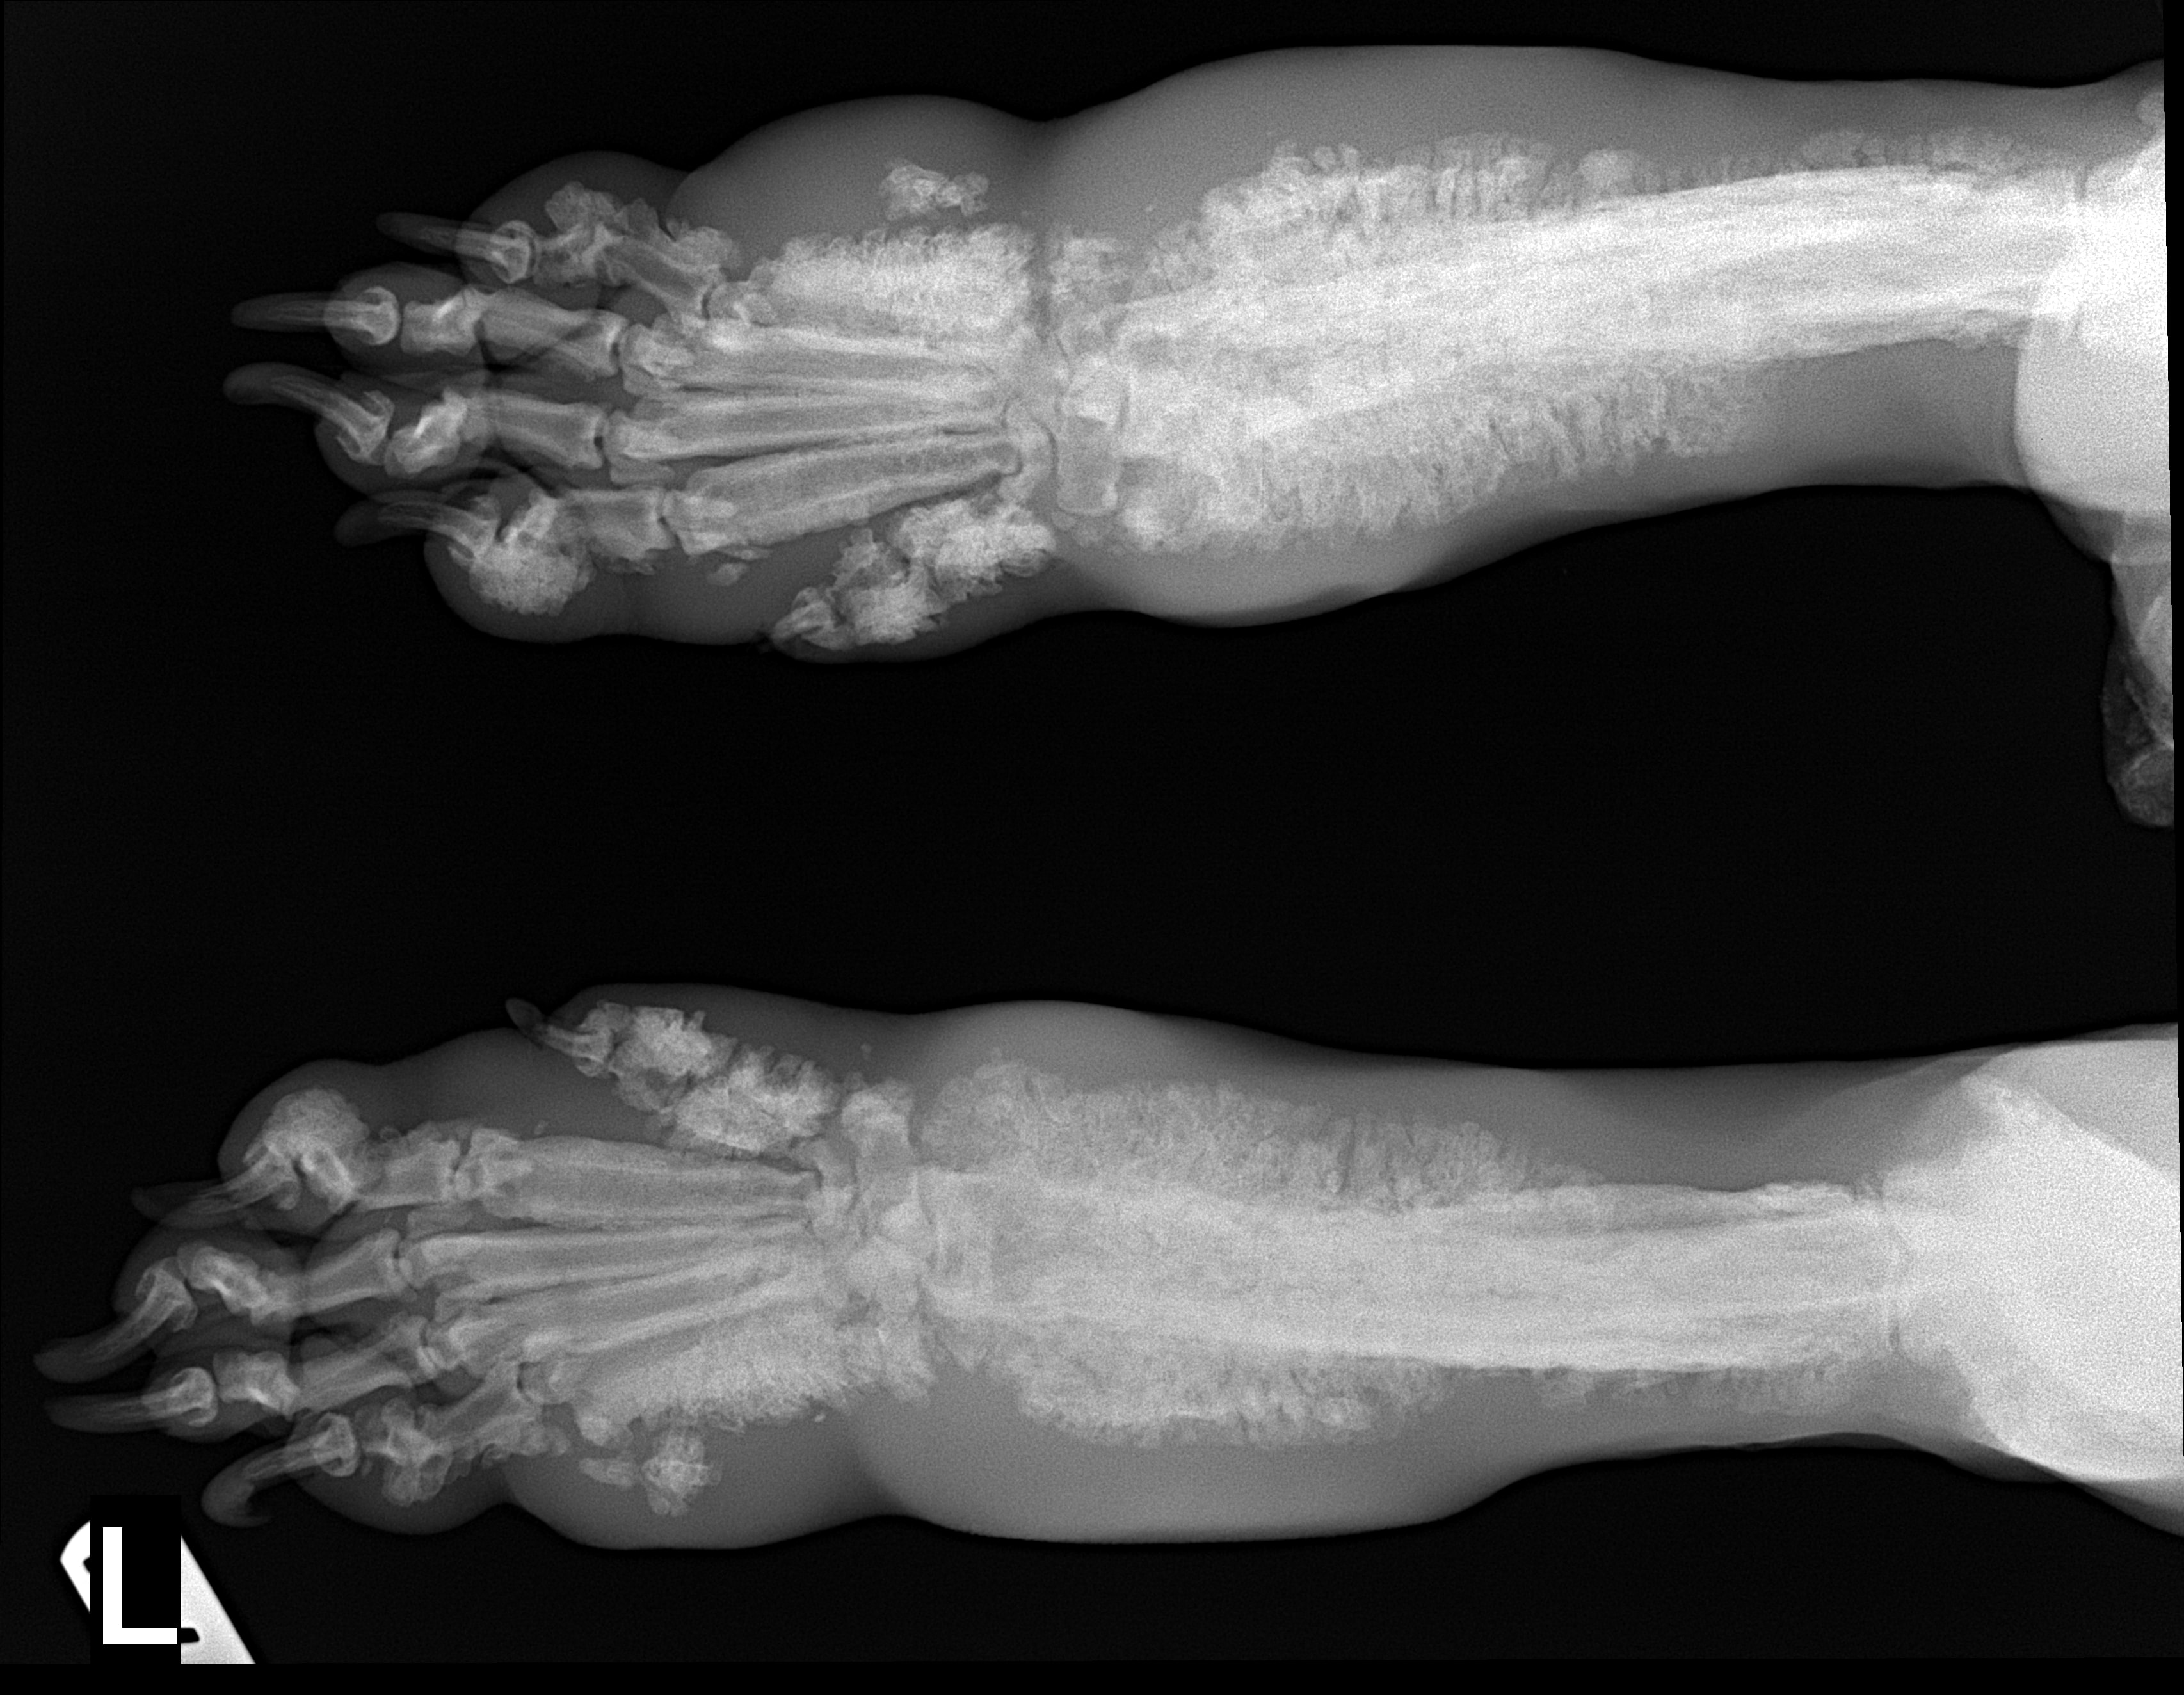

Species: Dog

Specimen: Radiograph

Shown: Hypertrophic osteopathy (Marie's disease) in pulmonary neoplasia